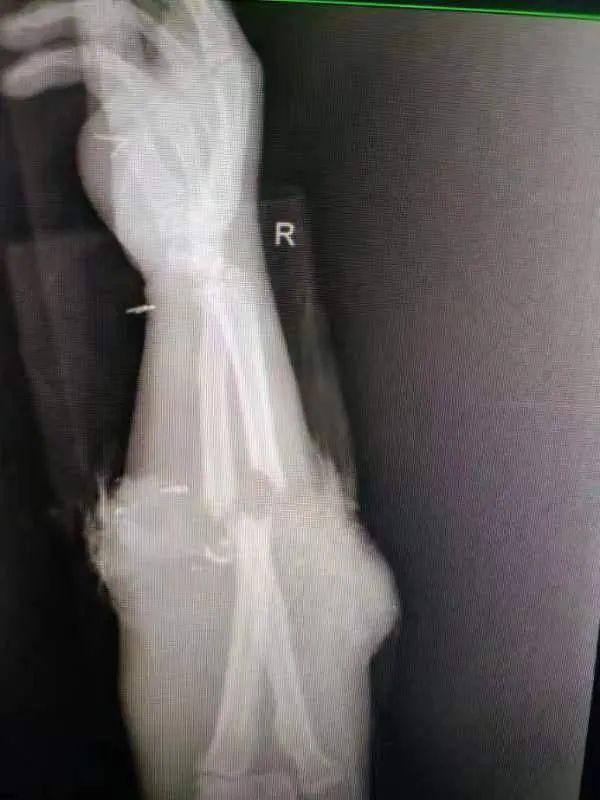

7 月 12 日中午,正在劳动中的王师傅(化名)右前臂不慎被皮带卷入机器中,强大的机械外力将他的右手死死夹卡吞噬。极度恐慌中他的右手被硬生生撕离身体,同事立即将王师傅紧急送往附近的三级医院武钢二医院进行救治。

二医院骨科吴峰主任立即组织抢救,因患者病情危重,手术难度大,吴主任立即启动两院联台手术机制。

总院骨科陈金武主任及关节手足外科王承良主任接到指令后立即赶赴二医院。这是一例典型的严重肢体辗压旋转抽脱离断伤,即使采取肢体再植的手术方式,肢体坏死率及残率仍然非常高。

两院骨科团队经过紧张的两个半小时手术,为保住王师傅右前臂迈出了成功的第一步。